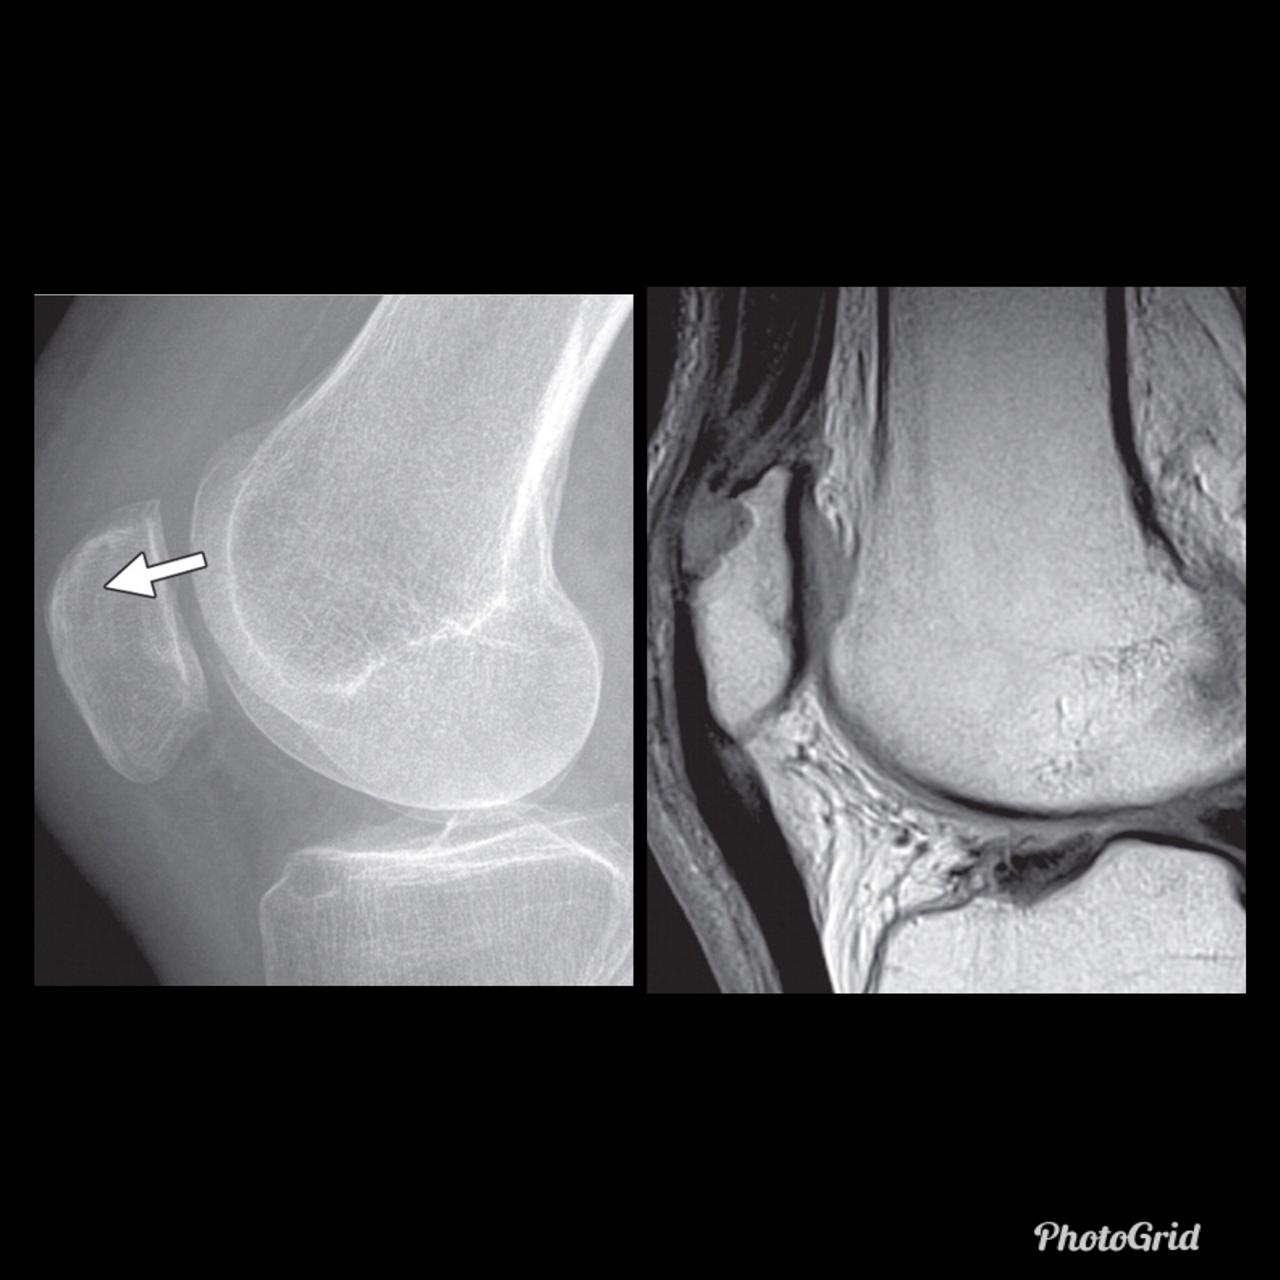

The fluid sign is one of the radiological features of osteoporotic fractures, and can be helpful in distinguishing them from metastatic vertebral fractures, as it is seen more often in osteoporotic fractures and is rarely seen in metastatic fractures.

The exact pathogenesis is not known, although proposed mechanisms include spontaneous avascular necrosis of the vertebral body (or Kümmell disease) or osteonecrosis at the site of an acute insufficiency vertebral fracture.

In fractured vertebral bodies, the fluid sign was adjacent to the fractured end plates and exhibited signal intensity isointense to that of cerebrospinal fluid on a background of diffuse hyperintensity in the vertebral body because of acute collapse.

It is seen in acute vertebral compression fractures that show bone marrow edema. In osteoporotic fractures, the fluid sign was significantly associated with fracture severity.